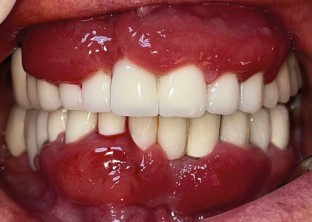

This report aims to present the clinical features, treatment approach, and management guidelines for plasma cell gingivitis (PCG) associated with nickel allergy. A 63-year-old woman was admitted to the clinic with complaints of gingival overgrowth and bleeding. Anamnesis and clinical examination revealed that she had been wearing metal-based fixed prostheses for 15 years. A complete blood count was performed and, after excluding malignancy, histopathologic evaluation revealed a diagnosis of PCG. A skin patch test confirmed nickel allergy, supporting the suspected link between the gingival condition and prolonged exposure to nickel-containing dental prostheses. Nickel levels in gingival tissues were evaluated using atomic absorption spectroscopy (AAS) before and after removal of restorations. AAS measurements detected 6.6 μg/g of nickel before removal and no more than blank analysis afterward. Following phase one and surgical periodontal treatment, and systemic steroid therapy, zirconium-supported prostheses were fabricated. The patient's gingival tissues returned to a healthy condition. This case report shows that PCG related to nickel allergy is characterised by gingival overgrowth with a fiery-red appearance. To confirm clinical findings, histopathological evaluation should include nickel quantification whenever possible. Treatment options should prioritise the elimination of nickel-containing prostheses, with substitution by all-ceramic restorations, to achieve resolution and prevent recurrence.